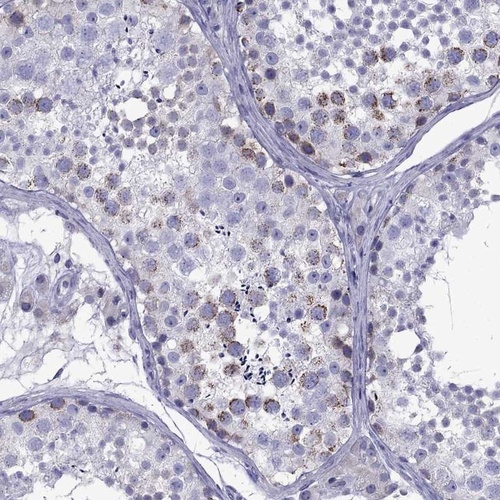

Immunohistochemistry analysis in human testis and endometrium tissues using Anti-TDRD1 antibody. Corresponding TDRD1 RNA-seq data are presented for the same tissues.